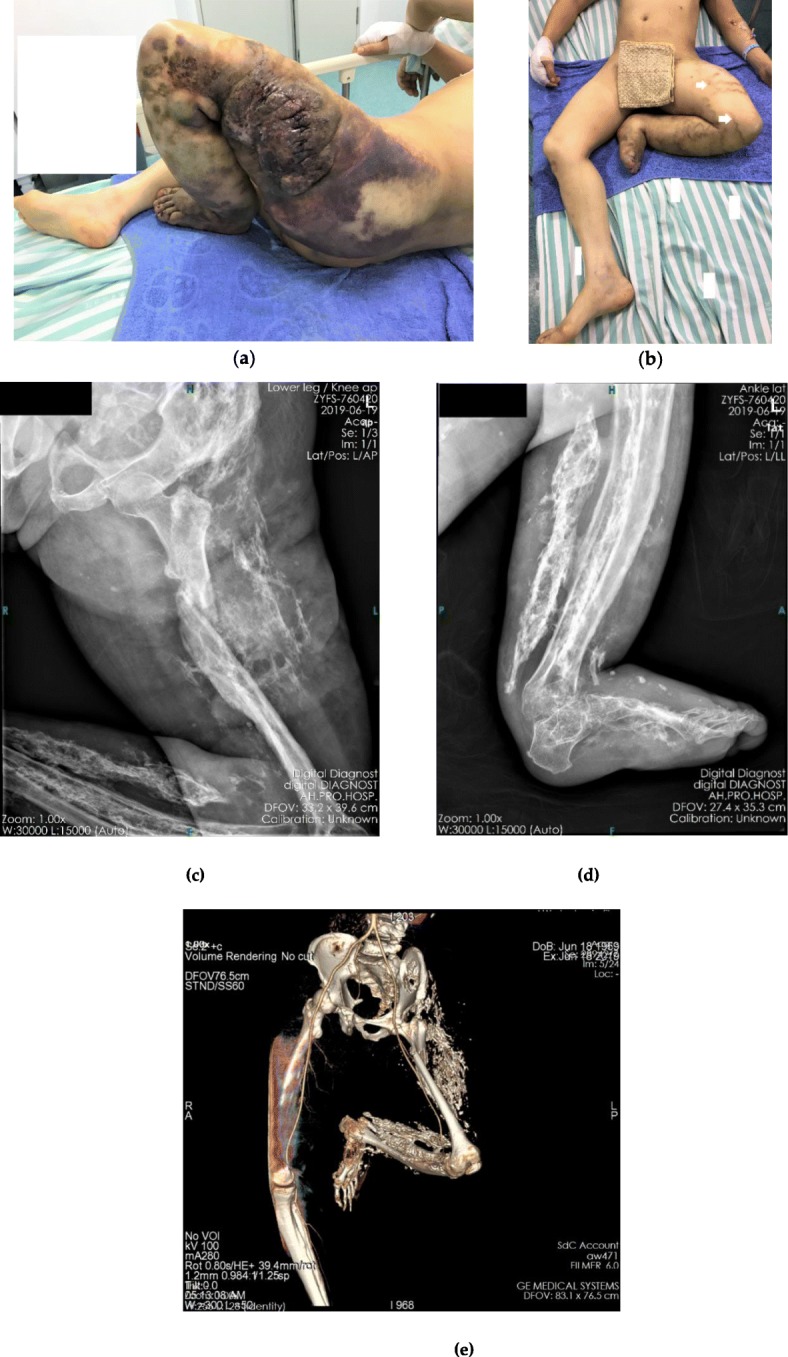

A 46-year-old man was transferred to our emergency department with a 15-cm stitched wound on a large kermesinus hemangioma-like lump on the left lateral thigh (Fig. 1a). The patient was hit by a car 1 day before. The patient was admitted immediately. The entire left lower extremity presented a compulsive contracture deformity with massive swelling, induration, and varicosities (Fig. 1b). Systemic examination revealed severe anemia, and an emergency transfusion was performed. Radiographs of the left leg showed a shaft fracture at the proximal third of the femur with extensive high-density shadows distributed in the flexor muscle side (Fig. 1c-d). Ultrasonography of the limb showed normal blood flow of the main vessels and venous malformations in the dermis. Three-dimensional computed tomography (CT) reconstruction confirmed a femoral fracture and a continuous artery with massive skeletal structural deformities along the extremity (Fig. 1e). The contralateral limb radiograph revealed a normal skeletal structure.

Fig. 1.

Photographs and images of the injury. a Initial presentation of hemangioma, a 15-cm stitched wound can be seen on the hemangioma; b Contracture of the leg, the white arrows show superficial varicose veins; c-d Radiograph showing femoral fracture and extensive high-density shadows distributed at the flexor muscle side of left lower extremity; e Three-dimensional computed tomography (3DCT). Vascular reconstruction shows coherence and integrity of the main arteries of the lower extremities